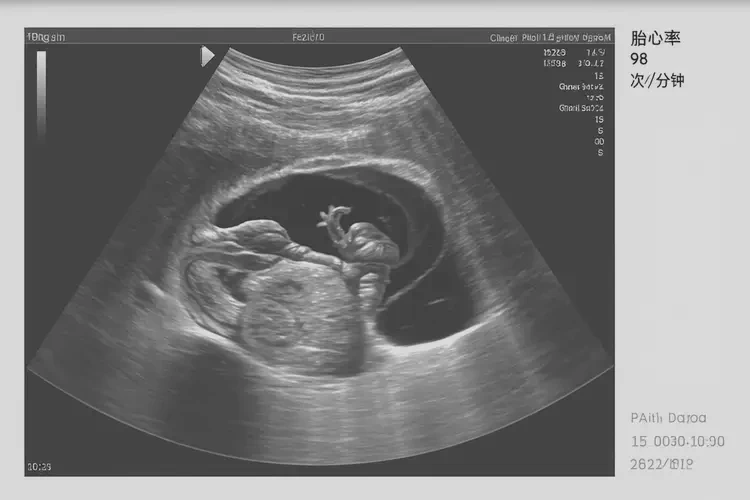

胎心96次/分钟在孕12周1天可能偏低。通常情况下,孕12周的胎儿心率应在120-160次/分钟之间。胎心率受多种因素影响,包括胎儿活动、母体状态等,因此一次测量结果并不能完全反映胎儿健康状况。

虽然胎心96次/分钟在孕12周1天可能偏低,但一次测量结果并不能完全反映胎儿健康状况。孕妇应定期监测胎心率,并在发现异常时及时咨询医生,以确保胎儿健康发育。